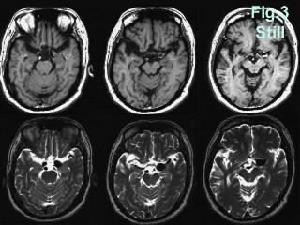

3.頭部核磁共振成像檢查可根據血腫的外形、血腫的占位效應(如腦室受壓變形、中線移位等徵象)以及血腫側腦皮質受壓徵象來診斷,其在急性期的陽性發現不及CT檢查。

MRI成像內板下透鏡狀高信號影,其強度變化與血腫期齡有關急性期呈低信號或等信號,亞急性及慢性期為高信號腦室、腦池變小,T2另權像上可見白質灰質交界處損傷灶伴高信號水腫區。